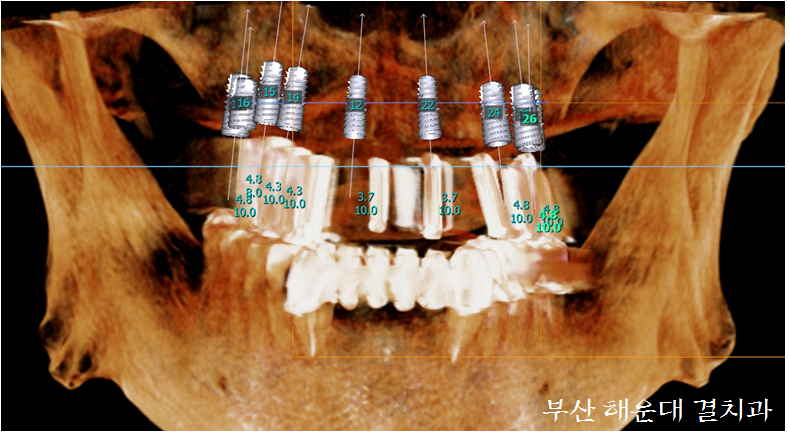

다음 내원에 제작된 CT촬영가이드를 입안에 끼우고 CT를 촬영합니다. 촬영 직후 CT영상을 통해 최적의 임플란트 개수와 식립 위치, 골이식 유무를 분석합니다.

CT분석 후 바로 환자분과 영상을 보며 상담을 진행하는데, 환자분 상황에 맞춰 임플란트 종류, 개수와 보철종류를 결정하게 됩니다.

환자분 귀가 후, 결정된 내용을 기반으로 수술 준비를 시작합니다. 컴퓨터 가상수술을 시행, CT촬영가이드의 방향 및 위치를 수정하여 임플란트 수술유도장치를 제작하고 수술에 필요한 임플란트의 종류, 임플란트 크기와 골이식 재료등을 준비 합니다.